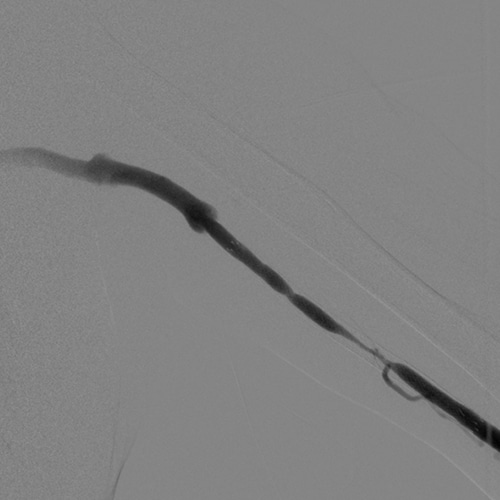

DSA

The DSA and roadmap functions make it suitable for intravascular procedures.